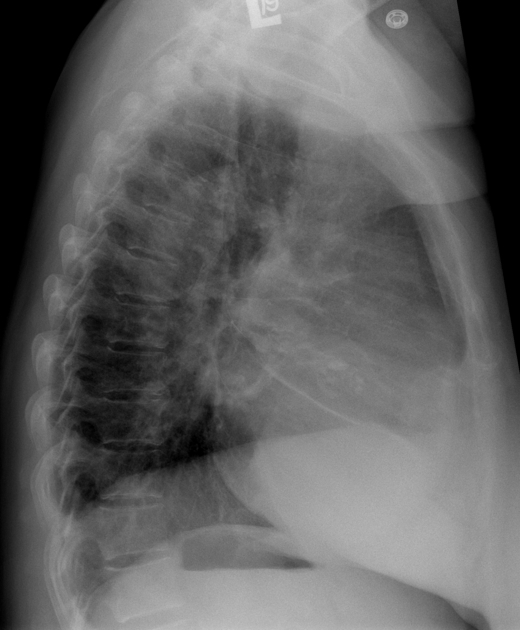

Гипертрофия левого желудочка: Причины и визуализация